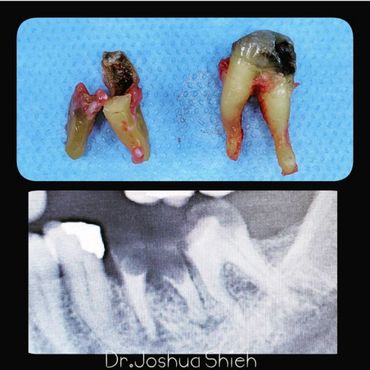

If the tooth is planned for extraction, an x-ray of the area will be taken to plan for the type of extraction.

Surgical Dental Extraction

A surgical extraction is a more complex procedure. It is used if a tooth may have broken off at the gum line or has not come into the mouth yet. Surgical extractions are commonly performed by general dentists or oral surgeons depending on the case. Sometimes it’s necessary to remove some of the bone around the tooth or to cut the tooth in half in order to extract it. For surgical extractions, patients receive local anesthetic. A suture is usually required to control bleeding and facilitate healing.